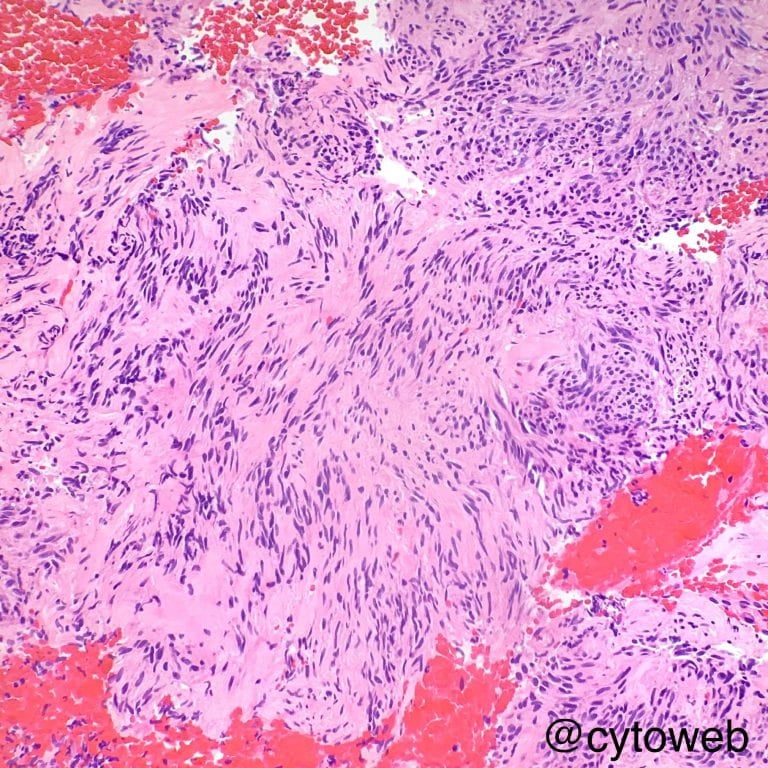

Musculoskeletal case 1

Musculoskeletal case 2